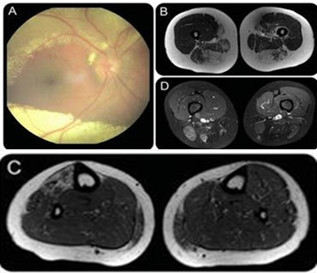

患者既往曾诊断为轻度症状性 Coats 病(CD,见图示)。肌肉 MRI 高度提示患者为 1 型面肩肱型肌营养不良(FSHD1,见图示)。基因检测证实了这一诊断。

图(A)眼底镜检查显示视网膜萎缩,视网膜周围大量渗出。肌肉 MRI 轴位像显示大腿后部肌肉和右侧胫前肌肉被脂肪组织所替代。B、C 为 T1 像,D、E 为 T2 压脂像

FSHQ1 是一种常染色体显性遗传性肌肉萎缩性疾病,但也会伴有除肌肉系统以外的表现,包括感音神经性耳聋,伴有毛细血管扩张的复杂性视网膜血管病变,比如 CD。在伴有视网膜脱落、视网膜微血管瘤形成和视网膜毛细血管形成风险的患者中,CD 可能是其特征之一。